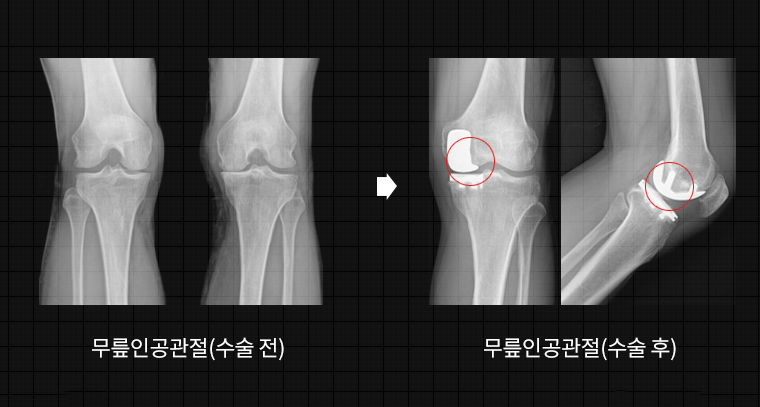

슬관절 인공관절 치환술이란?

여러가지 원인으로 인하여 손상된 무릎, 어깨, 족부 등의 관절부위를 인체에 무해하고 튼튼한 인공관절로 대체하는 수술법으로 심한 퇴행성관절염 치료의 대표적인 수술법입니다. 닳아 없어진 무릎 연골 대신 인체에 해가 없는 코발트크롬, 티타늄합금등의 금속이나 세라믹으로 만들어진 인공관절물을 골시멘트로 뼈에 부착하여 무릎 관절의 통증을 없애주고 운동 범위를 확보합니다.